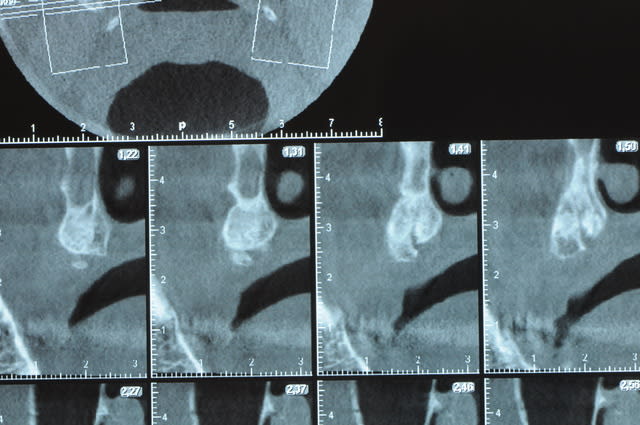

j'ai besoin de 4 implants au maxillaire pour faire tenir son complet.

dans la zone postérieur, pas de problème, mais devant, c'est une autre histoire.

Non sans décorner, superbe cas de début pour expansion, bone splitting et tout et tout.

la corticale a l'air tiptop, par contre en cas d'expansion il faut eventuellemnt augmenter le nombre d'implant à 6 pour compenser eventuellement le manque d'epaisseur 'avis personnel)

Je suis sceptique sur la gestion de ce cas par bone splitting puisqu'il met parait très difficile d'obtenir un volume osseux peri-implantaire crestal suffisant et satisfaisant.

+1 Olive, ce serait à mon avis plus prédictible avec des greffes. Je doute qu'on puisse obtenir suffisamment d'os en vestibulaire et en palatin des implants en splittant une crête aussi fine.

J’ai pratiquement les mêmes résultats que dans l’implanto classique, si j’ai 3 mm d’os en épaisseur.

Si je dispose de 2mm j’ai encore 85% de succès

À environ 1,5 mm je descends à 50% (c’est bas mais ça veut dire qu’un cas sur deux bénéficie d’implants alors que normalement ......)

De ce que j’ai vu du cas de D57 c’est me semble t il un magnifique cas d’expansion, ce qui ne veut pas dire rien d’autre

Une petite étude de ton cas D57

Sous réserves bien sur de voir l’animal en vrai

Les zones exploitables radiologiquement parlant:

Coupes implant

2,3 40100

4,96 35130 avec sinus lift mais difficile

5,25 35150

6,02 35130

6,78 35115 après réduction de hauteur de crête

7,26 35115 après réduction de hauteur de crête

8,51 35150

10,43 40115 ou 50115

11,10 40115

Ce qui nous fait 9 implants possible évidement avec un comblement de sinus on augmenterait encore les zones implantable mais ce n’est pas le but recherché, avec 8 (4+4) il doit être possible de faire une belle barre support de complet